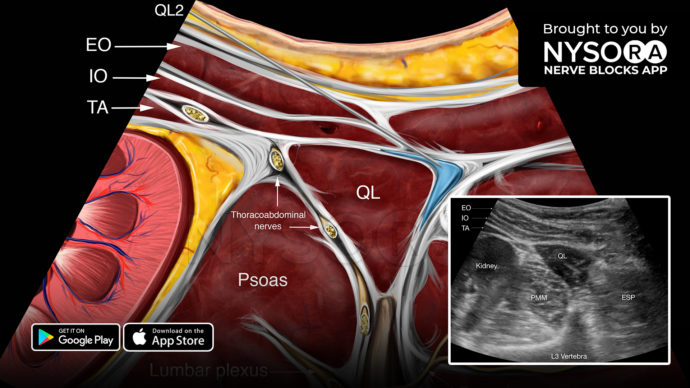

10. Transversus Abdominis Plane (TAP) Block